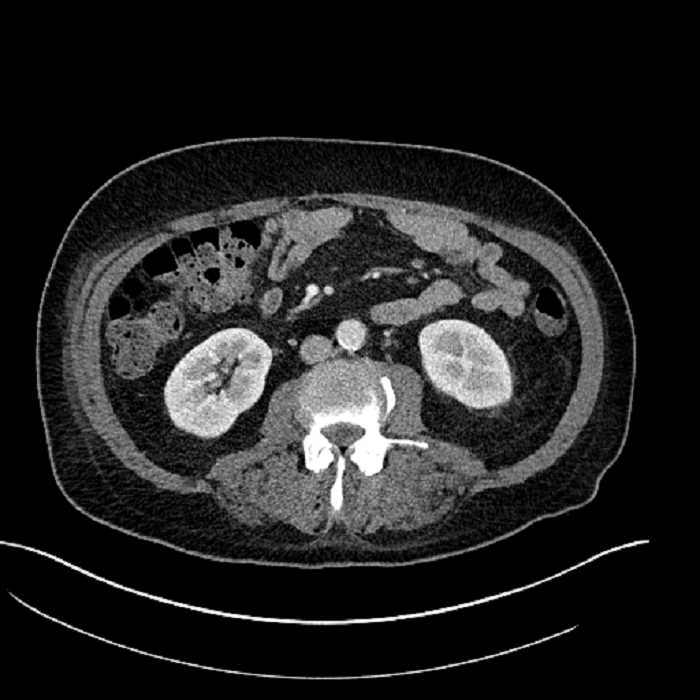

• Large fluid density structure in hepatic segments 7 and 8 measuring 10 x 7 x 7 cm with internal septation and circumferential ill-defined low density compatible with edema

• Peripherally enhancing subcapsular collections along the anterior margin of the left hepatic lobe measuring 3 x 1 cm and 2 x 1 cm

• Clearly marginated fluid density structure in segment 7 and several other scattered tiny hypodensities, which likely represent cysts

Acute sigmoid diverticulitis complicated by a small contained perforation and a large abscess in the right hepatic lobe. Additional small subcapsular abscesses along the anterior margin of the left hepatic lobe.

• The classic CT imaging appearance is a double target sign with internal low density surrounded by an internal enhancing rim (capsule) and a low density external rim (edema)

Hepatic abscess showing the double target sign with low density internally surrounded by a thin inner enhancing rim (red arrow) and ill-defined outer low density rim (yellow arrow). Blue arrow indicates an internal septation. Red arrows: additional smaller subcapsular abscesses. Red arrow: focal contained perforation associated with diverticulitis.